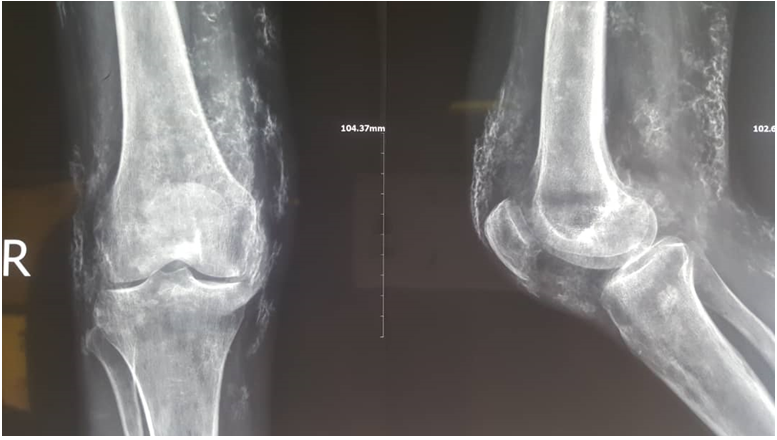

AP radiograph of the pelvis showed extensive subcutaneous calcifications involving the gluteal regions and the lateral aspect of the upper both thighs. The visualized muscle bundles appear free. Bones are unremarkable. AP and lateral radiograph of the RT knee shows florid flakes of calcifications within the subcutaneous fat planes with no evidence of muscle or tendon calcification. All features are in keeping with calcinosis cutis.

Figure 2 Lateral radiograph of the RT knee shows florid flakes of calcifications.